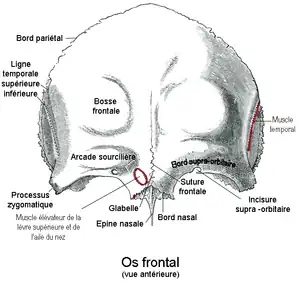

Bord supra-orbitaire

Le bord supra-orbitaire (ou bord supra-orbitaire de l'os frontal ou arcade orbitaire) est le bord supérieur de l'orifice orbitaire formé par le bord saillant situé entre la partie convexe supérieure dite portion frontale et la partie inférieure horizontale dite portion orbito-nasale de la face antérieure de l'os frontal.

Il est situé entre latéralement le processus zygomatique de l'os frontal et médialement l'épine nasale de l'os frontal.

Il est concave en bas et marqué par l'incisure supra-orbitaire.

Paroi supérieure de l'orbite

La paroi supérieure de l'orbite (ou toit de l'orbite ou voûte orbitaire) est formée à l'avant par la face orbitaire de la partie orbitale de l'os frontal et à l'arrière par la face inférieure de la petite aile de l'os sphénoïde percée du canal optique.

En avant et en dehors la paroi présente la fosse de la glande lacrymale. En avant et en dedans, elle présente la fosse trochléaire.